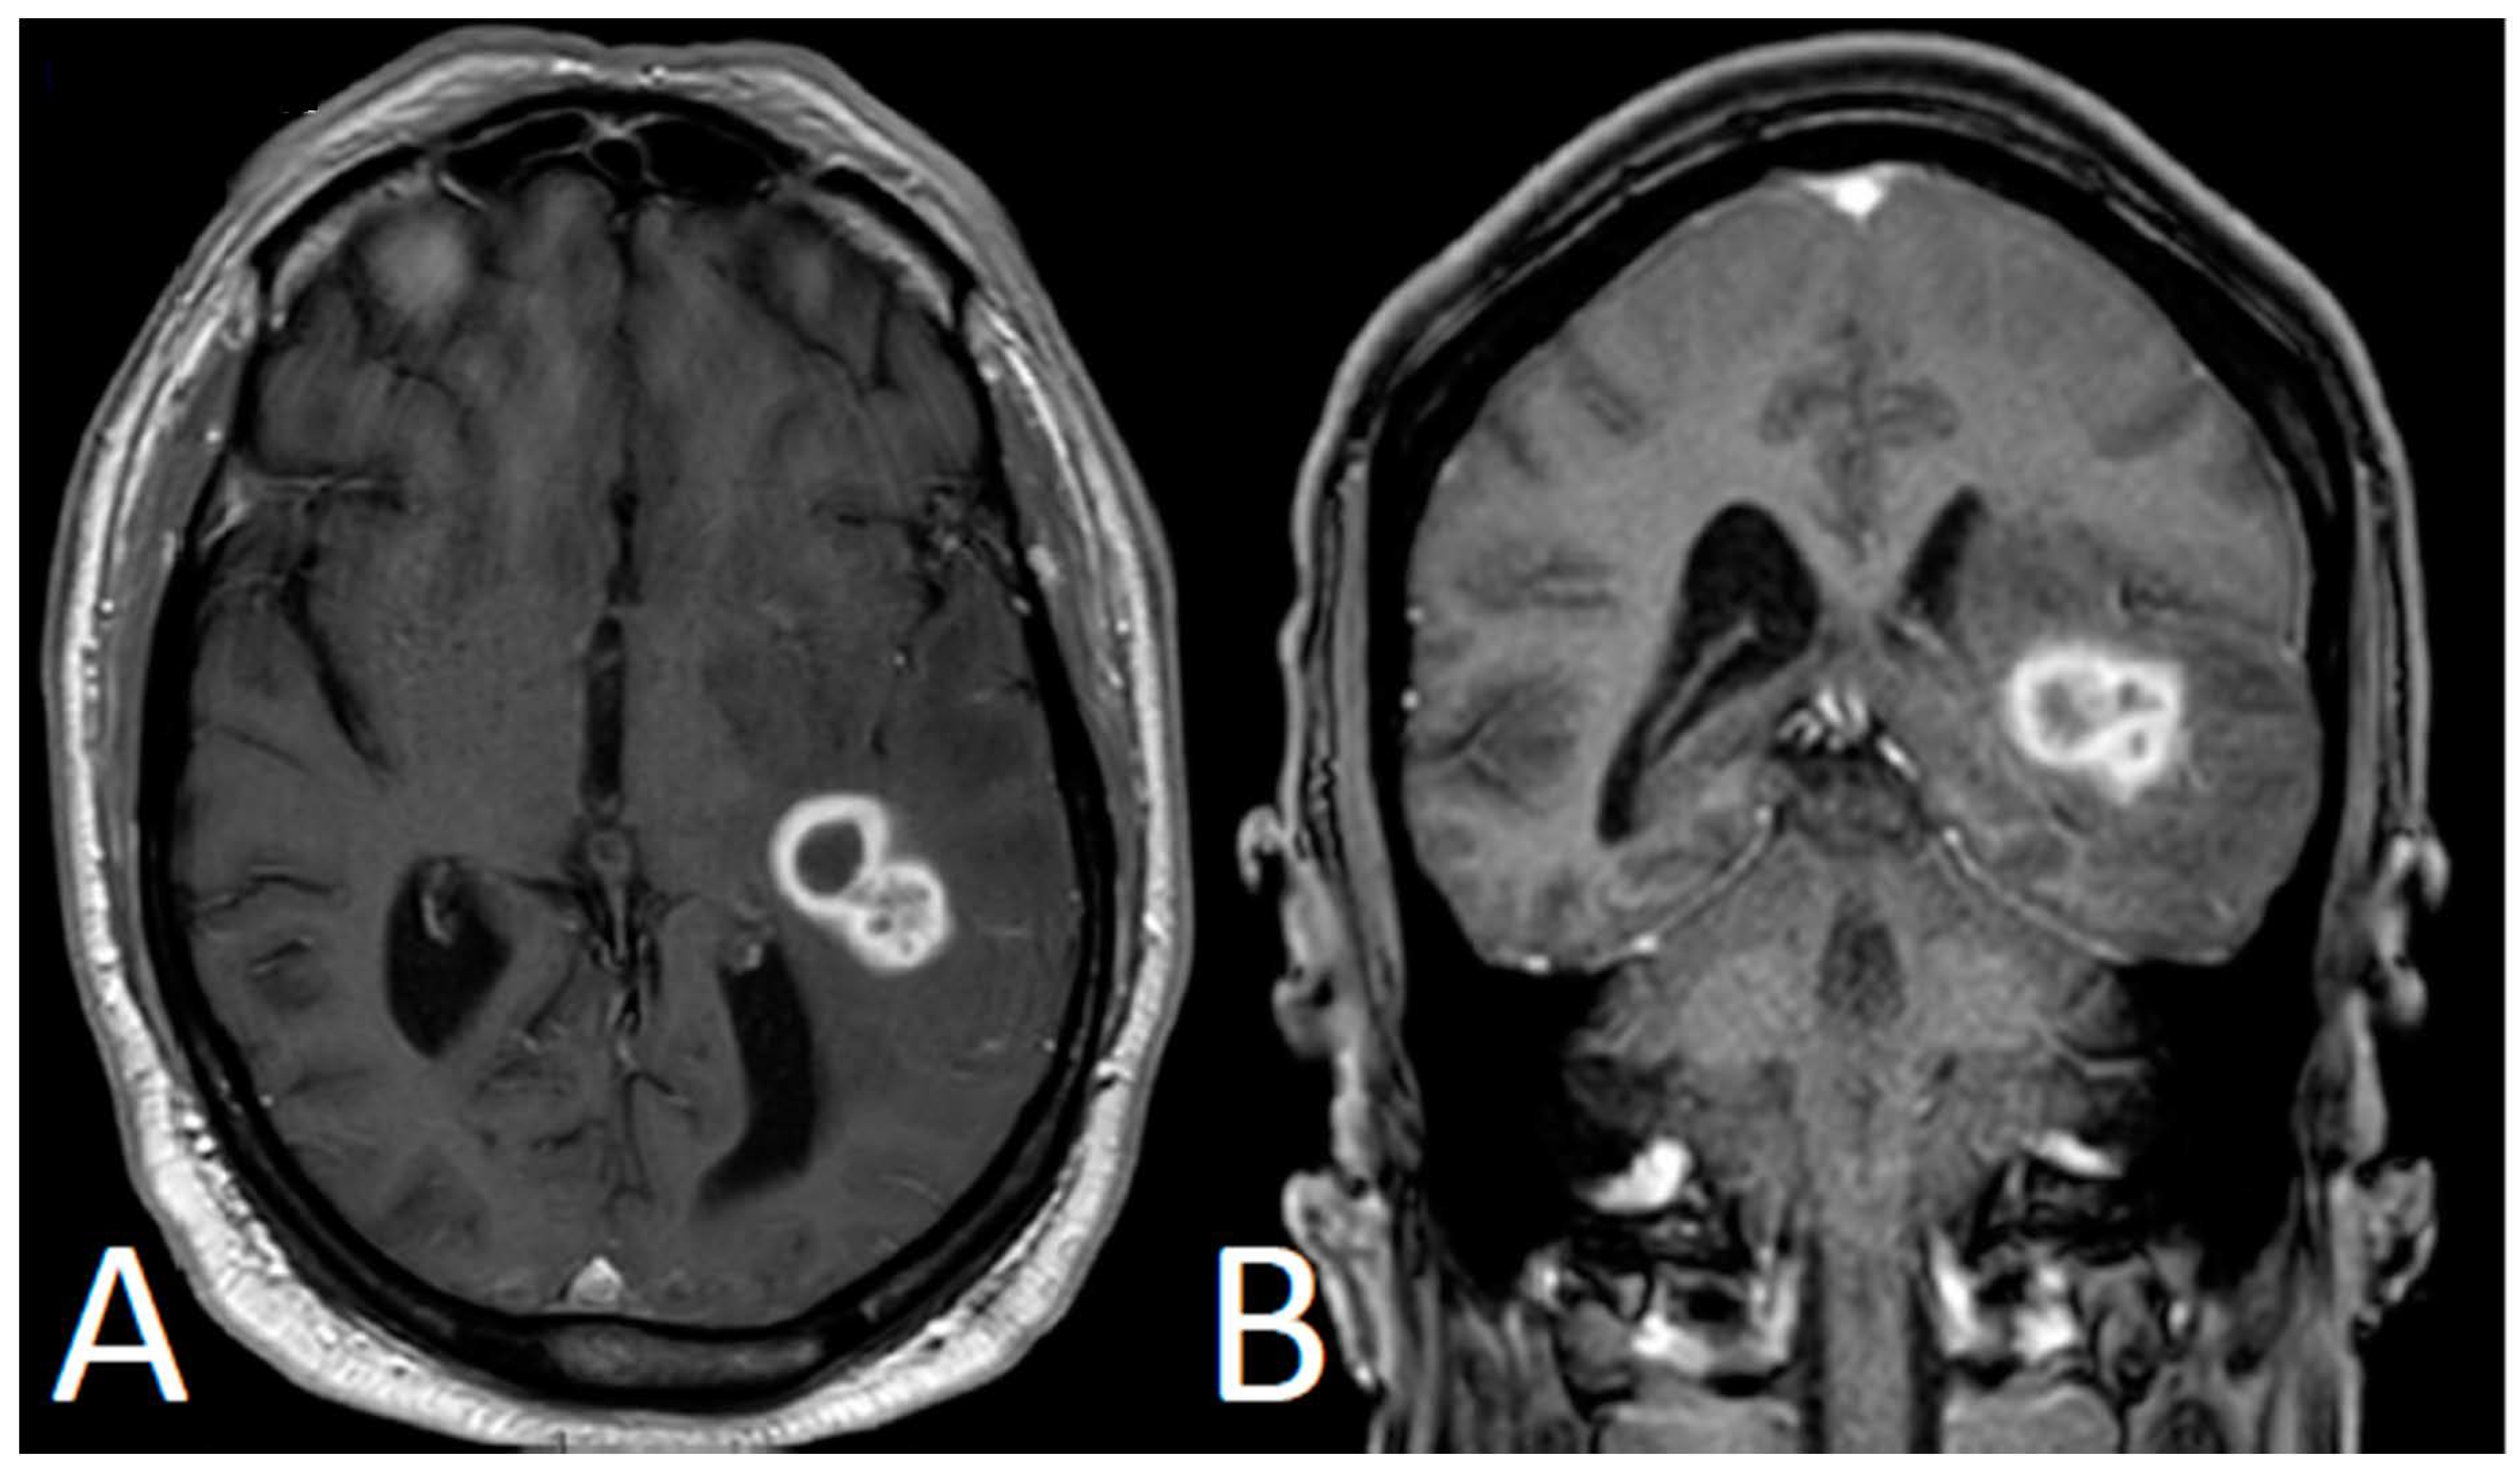

After Cycle 3, the patient’s caregiver noticed episodes of confusion and slurred speech. Brain magnetic resonance imaging (MRI) revealed a left temporal lobe mass with peripheral enhancement measuring 2.4 × 1.7 × 1.7 cm (Figure 1). He did not exhibit symptoms of infection; however, he was admitted to the hospital and was started on broad-spectrum antibiotics. He, then, underwent MRI spectroscopy, which raised the possibility of a neoplastic process (primary or metastasis). A complete re-staging CT scan of the body showed an improvement of the CLL/SLL lymphadenopathy, with no radiologic evidence of a second primary malignancy.

Figure 1.

Brain MRI showing lobulated left temporal mass with peripheral enhancement with surrounding cerebral edema (A: axial view; B: coronal view).